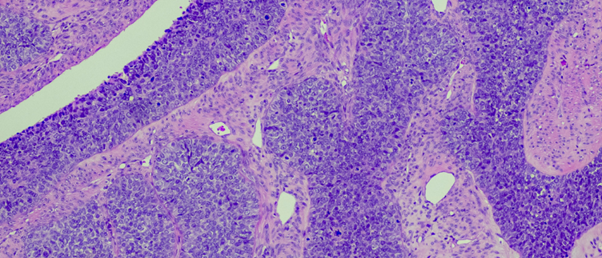

The researchers used SEEP to analyze three types of lab models created from human ovarian cancer cells: spheroids, organoids and mouse models. To do so, tissue samples from these models were submerged in a bath containing the fluorescent dye, the cells are then barcoded, single-cell RNA sequenced and then computationally analyzed, to deliver spatially resolved single-cell RNA-sequencing data.

The SEEP method demonstrated that tumor cells near the surface were more likely to undergo cell division and turn on genes to protect them from the immune system than those located at its center. This validates previous understanding of the relationship between cell state and position within a tumor.